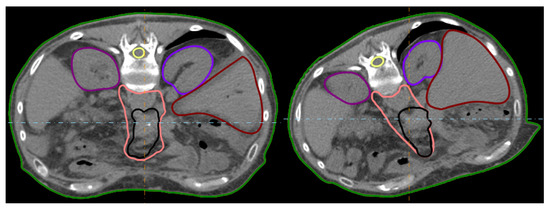

2.1. Patient Data, Imaging and Treatment Workflow